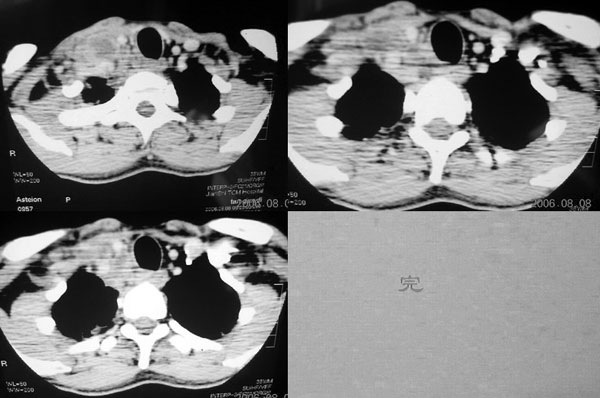

患者,谭××,男,35岁,右颈部肿痛一周,体温39度。增强待续,伪影大,对不起,请大家凑合……

右颈部肌肉、血管间隙内可见不规则肿块,强化后呈多房性,间隔及壁线样强化,考虑颈部脓肿。

多发肿大淋巴结,呈环形持续性较明显强化,部分相互融合,结合临床,考虑炎性.

颈部血管间多房囊性肿块,边缘模糊,增强囊壁有强化,中间低密度区无强化。从强化特点支持颈部神经鞘瘤及淋巴性肿瘤。但病人病史较短,且有高热,病灶边缘模糊,又都不支持。神经鞘瘤及淋巴性肿瘤多边缘清楚。因此还是考虑炎症。

中心性坏死,环行强化支持:(1 淋巴结核)(2 脓肿) 临床高热,后者可能性更大 。神经鞘膜瘤不会广泛弥漫性的延续至上纵隔。